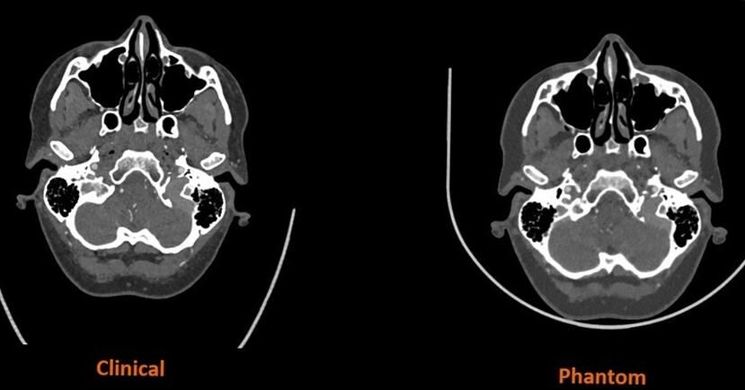

Gondolt már arra, hogy a CT-szkennerek hogyan képesek az emberi testet ilyen részletgazdagon ábrázolni? A titok nyitja részben az úgynevezett fantomokban rejlik, amik az orvosi képalkotó eszközök kalibrálására és ellenőrzésére készülnek. Ezek a modellek olyan pontosan adják vissza az emberi test szerkezeti és radiológiai tulajdonságait, hogy segítenek a pontos diagnózis felállításában és az eszközök beállításában.

A fantomok alkalmazása nemcsak a képalkotási technikák megbízhatóságát növeli, hanem a diagnosztikai precizitást és hatékonyságot is fokozza. 3D nyomtatók segítségével elkészített modernebb modellek révén még pontosabb és személyre szabottabb megoldások érhetők el az orvosi gyakorlatban.